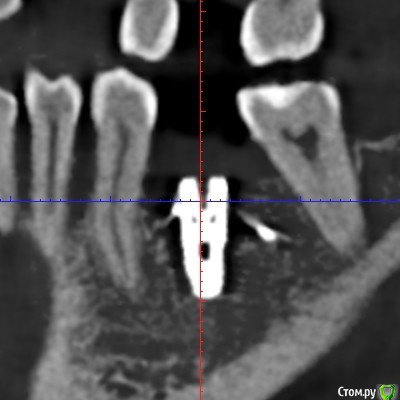

Irina_S Опубликовано 6 января, 2018 Поделиться Опубликовано 6 января, 2018 Здравствуйте, уважаемые спеицалисты! С наступившим вас Новым годом!!! В конце августа были установлены три имплантата Xive - 36, 46, 47. Одновременно с установкой выпиливалась кость и прикручивалась винтиками в те места, где по мнению хирурга её не хватало. В середине октября сквозь десну с язычной стороны стали просматриваться верхушки имплантатов 36 и 46. Во время периодических осмотров врач говорил, что всё в порядке.В декабре пришло время установки формирователей десны. Установивший имплантаты хирург стал работать в другой клинике. Он пригласил на осмотр, сказал, что надо будет добавить десну в области 36 и 46, взяв кусочки с нёба, а с самими имплантатами всё хорошо, можно одновременно с пластикой десны ставить формирователи и через 2-3 недели отправляться к ортопеду.Следуя логике сохранения гарантии на установку имплантатов, которую даёт не врач, а клиника, я пошла к другому хирургу в ту клинику, где устанавливались имплантаты. Он посмотрел на выступающие верзушки имплантатов, причём 36 успел к этому времени уже прорвать десну. Посмотрел КТ и сказал, что предварительно видит проблемы и помимо пластики десны может понадобиться переустановка имплантатов. Самый проблемный, по его мнению, 46, а 36 - под вопросом. Сказал, что окончательное решение можно будет принять только после разрезания десны, чтобы увидеть фактическую ситуацию. Причём переустановка - по гарантии, и она будет делаться сразу - выкручивается старый имплантат и ставится новый, тоньше (3,8мм вместо 4,5мм) и длиннее. Соответственно, в этом случае снова ждать 3-4 месяца, и только после этого ставить формирователи. Присутствовавший на консультации ортопед был полностью с ним согласен и сказал, что на имплантаты в таком состоянии, как он их видит на КТ, он коронки ставить не будет. Аргументировалось тем, что кости в принципе достаточно, но имплантаты надо было устанавливать глубже, а так, как сейчас, они протянут максимум 3-4 года, а потом расшатаются и выпадут. Клиника даёт гарантию 10 лет, поэтому они считают, что нужно хорошо установить изначально.На месяц раньше ставились имплантаты в верхнюю челюсть, с ними всё хорошо. Но, рассматривая проекции КТ, я вижу обширные тёмные области в районе всех имплантатов как дефект засветки при формировании КТ. В связи с чем вопрос: может ли картина на КТ с отсутствием видимой костной ткани происходить из-за самого оборудования, на котором делается КТ, и не совсем соответствовать действительности? Иначе, есть ли шанс, что при вскрытии десны окажется, что с расположением импллантатов всё в порядке (как и уверяет "сбежавший" их этой клиники хирург), а альтернативное мнение связано в некотором роде с желанием опозорить уволившегося сотрудника и удержать пациента у себя, ведь потом предстоит большая ортопедическая работа? И ещё один вопрос: чего мог категорически не принимать ортопед, говоря, что в подобных случаях он всегда отправляет к хирургу, если заведомо было известно, что недостающая десна в любом случае будет наращиваться?С имплантатом 47 ситуация, вроде бы, не такая критическая. Это на самом деле так? Ссылка на комментарий

колесников Опубликовано 6 января, 2018 Поделиться Опубликовано 6 января, 2018 С десной однозначно предстоит поработать. Импланты расположены несколько язычно,что может быть проблематично. Ссылка на комментарий

колесников Опубликовано 6 января, 2018 Поделиться Опубликовано 6 января, 2018 Сколько врачей,столько и клинических подходов. Я бы переустановил нижние импланты заменив ксайв на Штрауман тл, плюс увеличил объём мягких тканей по гребню.Это ,как говорится ,обойтись малой кровью с благоприятным прогнозом. Если оставлять этот ксайв,то только пластики десны не достаточно,придётся перекрывать их костным материалом с мембраной и позднее Увеличить объём мягких тканей. Все бы ничего,но меня смущает язычное положение платформ имплантов и их уровень относительно соседних зубов. Это лично моё мнение,оно может отличаться от мнений коллег. Ссылка на комментарий